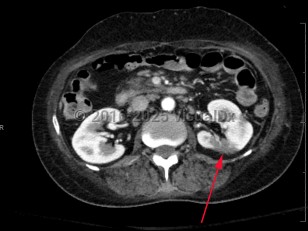

Renal infarction

Atrial fibrillation is the most common cause overall, but infectious endocarditis, renal artery occlusion following aortic or renal interventions, polyarteritis nodosa, trauma, underlying hypercoagulable states, and cocaine use are other etiologies.

Renal infarction is felt to be a rare condition with incidence varying based on study: 1.4% in autopsy studies and 0.007% based on emergency department data. However, it is also an underrecognized condition and often missed.

Symptoms often mimic other renal pathology, including acute onset of flank pain or abdominal pain, hematuria, and occasionally fever or vomiting; thus, diagnosis can be delayed. Physical examination findings include acute hypertension and, rarely, other signs of extrarenal embolization, including focal neurologic deficits.